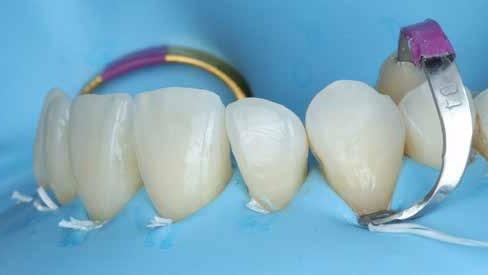

Az alábbi cikkben egy I. osztályú üreg thermo-viszkózus kompozittal, okkluzális matrica technikával történő ellátásának lépéseit ismertetjük (1. ábra). A kofferdám felhelyezését követően az okkluzális felszín anatómiai karakterisztikáját átlátszó, folyékony, fényrekötő kompozit (Clip Flow, VOCO) segítségével rögzítettük. Az anyagot egy bondecset alkalmazásával vittük fel a fog okkluzális felszínére, majd 10 másodpercen keresztül polimerizációs lámpával megvilágítottuk (2–4. ábra). A megkötött átlátszó okkluzális matrica ellenőrzését követően (5. ábra) alkoholba helyeztük (ethanol vagy izopropil-alkohol), az oxigén inhibíciós réteg eltávolítása érdekében. Ezután a szuvas foganyagot eltávolítottuk (6–7. ábra). A zománcot 30 másodpercig, a dentint pedig 15 másodpercig savaztuk (DeTrey Conditioner 36, Dentsply Sirona), majd a felszínt levegő-vízspray segítségével lemostuk (8 –10. ábra). Mivel a fogbélkamrát már csak egy vékony réteg ép dentin fedte, ezért a pulpa vitalitásának megőrzése érdekében az üreg pulpális falait védőréteggel fedtük (DeTrey Conditioner 36, Dentsply Sirona) (11. ábra). Az adhéziót Futurabond DC (VOCO) felhasználásával biztosítottuk. A bondot bondecsettel 20 másodpercen keresztül az üreg falaiba masszíroztuk, majd 5 másodpercen keresztül olajmentes levegő spray-vel megfújtuk a felesleg eltávolítása és a bondréteg elvékonyítása érdekében. A bondot ezt követően 10 másodpercen keresztül polimerizációs lámpával megvilágítottuk (12–13. ábra). Az üreg alját nagyon vékonyan folyékony kompozitréteggel fedtük (GrandioSO Light Flow, A3.5, VOCO), amelyet 20 másodpercen keresztül polimerizációs lámpával megvilágítottuk (14–15. ábra). A bulk-fill tömőanyagot (VisCalor bulk, A2) egy olyan kézi applikátor

2. ábra: A kofferdám felhelyezése. – 3. ábra: A Clip Flow felvitele bondecset segítségével. – 4. ábra: A Clip Flow megvilágítása.